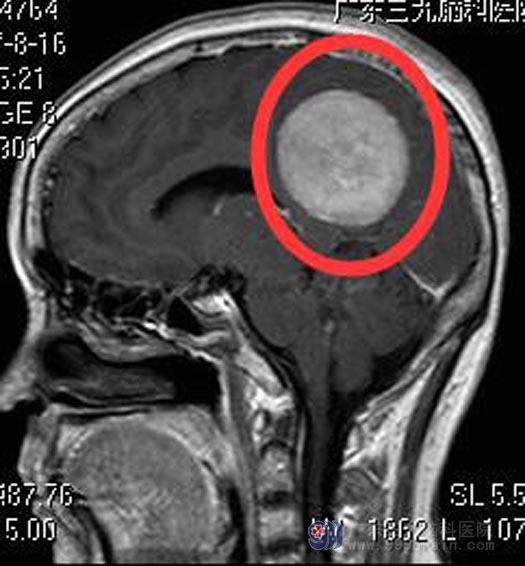

广东三九脑科医院进一步头颅MR检查提示:顶部镰旁(左侧为主)占位性病变,大小约5.4cm×5.4cm×5.2cm,考虑脑膜瘤;头颅CTA检查提示占位性病变血供丰富。经过全身检查,陈女士没有明显的手术禁忌症,家属积极要求手术切除。

综合神经外科鲁明主任主刀,在全麻下行左侧顶部大脑镰巨大脑膜瘤切除术,术中显微镜下见肿瘤部分呈灰白色,质地中,血运丰富,全切肿瘤,手术顺利。术后陈女士神志清醒,回答正确,四肢活动正常,满意出院。术后病理回报:脑膜瘤。